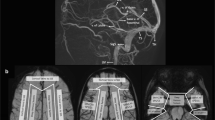

Understanding the venous drainage pathways of the brain is important to allow accurate diagnosis of venous-related injury and to localize the source of venous disease. This is particularly true in the setting of focal venous disease such as venous thrombosis. Figure 1 demonstrates the major cerebral venous drainage territories. It is important to note that the venous drainage territories of the deep and superficial cerebral veins are variable, although the generalized drainage areas can be estimated [1]. The superior sagittal sinus drainage territory comprises the majority of the superior cerebrum. The sylvian veins drain the peri-insular region and drain into the basal dural sinuses (sphenoparietal and cavernous sinuses.) The transverse sinuses drain blood from the lateral surfaces of the temporal, parietal and occipital lobes. The vein of Labbe´, if dominant, can comprise much of the transverse sinus drainage territory. The deep medullary veins, which are tributaries of the thalamostriate and septal veins, drain the deep gray structures, deep white matter and deep central midline cortex. The thalamostriate and septal veins coalesce into the internal cerebral veins.

Supratentorial venous territories (a–d). Gray superior sagittal sinus drainage territory, white sylvian veins, black transverse sinus territory (vein of Labbe´), speckled white thalamostriate veins (drain to internal cerebral veins), black stripes septal veins (drain to internal cerebral veins) and inferior sagittal sinus